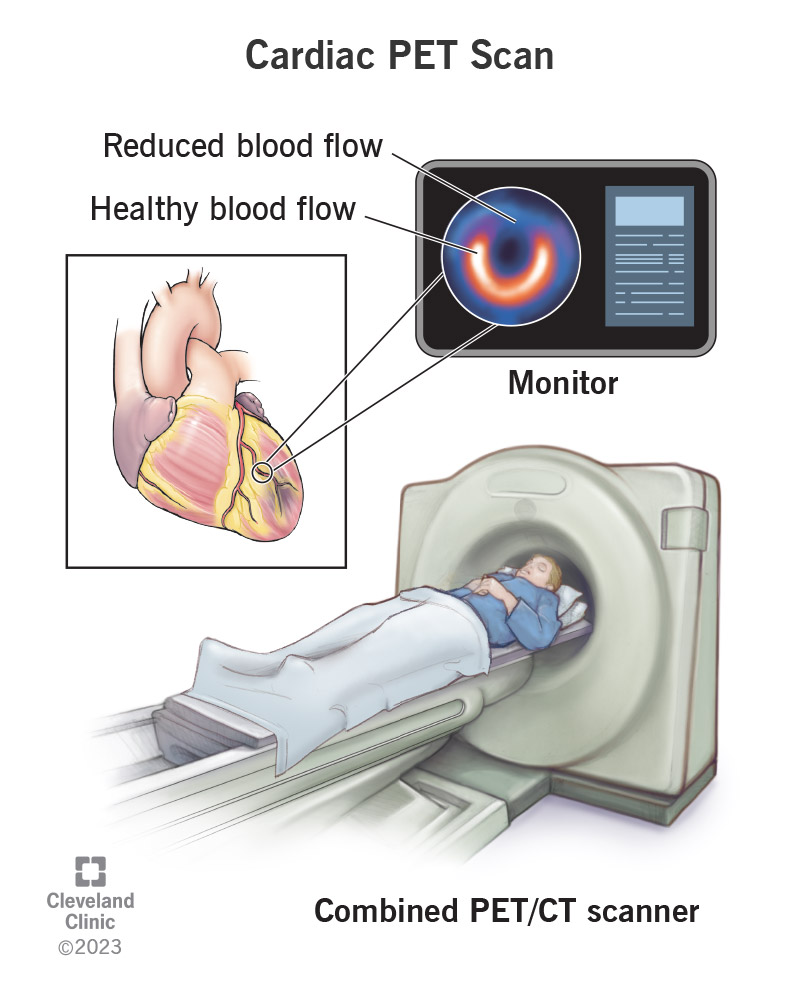

Enhance your business with our stunning commercial Cardiac Pet/ct collection of numerous professional images. optimized for commercial use with truck, vehicle, and automobile. ideal for corporate communications and branding. Discover high-resolution Cardiac Pet/ct images optimized for various applications. Suitable for various applications including web design, social media, personal projects, and digital content creation All Cardiac Pet/ct images are available in high resolution with professional-grade quality, optimized for both digital and print applications, and include comprehensive metadata for easy organization and usage. Discover the perfect Cardiac Pet/ct images to enhance your visual communication needs. Our Cardiac Pet/ct database continuously expands with fresh, relevant content from skilled photographers. Reliable customer support ensures smooth experience throughout the Cardiac Pet/ct selection process. Professional licensing options accommodate both commercial and educational usage requirements. Multiple resolution options ensure optimal performance across different platforms and applications. Regular updates keep the Cardiac Pet/ct collection current with contemporary trends and styles. Each image in our Cardiac Pet/ct gallery undergoes rigorous quality assessment before inclusion. Time-saving browsing features help users locate ideal Cardiac Pet/ct images quickly. The Cardiac Pet/ct archive serves professionals, educators, and creatives across diverse industries. Comprehensive tagging systems facilitate quick discovery of relevant Cardiac Pet/ct content.